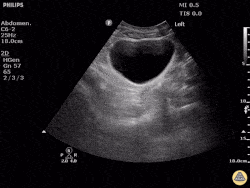

What quadrant are we in?

This is a RUQ view, also known as a right flank view or perihepatic view. The predominant organ in this view is the liver with Morrison's pouch directly below, between the liver and kidney.